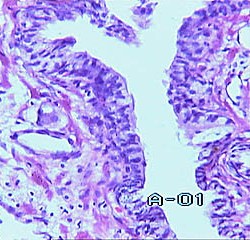

Переходноклеточный рак - эпителиальная опухоль предстательной железы, развивающаяся из протокового эпителия, либо из метаплазировавших в преходный эпителий ацинарных эпителиоцитов. Опухоль представляет из себя ворсины, состоящие из тонких соединительнотканных прослоек, содержащих кровеносные сосуды и покрытых атипичными клетками переходного эпителия (I степень дифференцировки). При уменьшении степени дифференцировки, клетки паренхимы опухоли становятся более и более атипичными, появляются картины атипических митозов и поля солидного строения (II степень дифференцировки). Опухоль состоящая из резко атипичных клеток, содержащая большое количество митозов и имеющая солидное строение - может трактоваться как переходноклеточный рак III степени дифференцировки. Однако, в структуре переходноклеточного рака, не только II но и III степени, практически всегда можно отметить выраженную тенденцию к стратификации эпителиоцитов, даже если они представлены крайне атипичными вариантами.